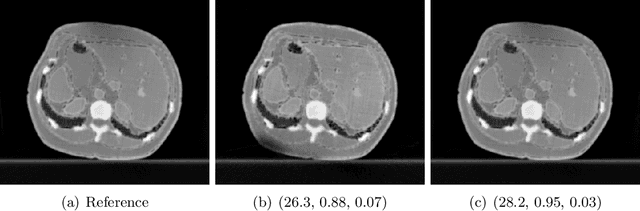

Abstract:Quantitative comparison of the quality of photoacoustic image reconstruction algorithms remains a major challenge. No-reference image quality measures are often inadequate, but full-reference measures require access to an ideal reference image. While the ground truth is known in simulations, it is unknown in vivo, or in phantom studies, as the reference depends on both the phantom properties and the imaging system. We tackle this problem by using numerical digital twins of tissue-mimicking phantoms and the imaging system to perform a quantitative calibration to reduce the simulation gap. The contributions of this paper are two-fold: First, we use this digital-twin framework to compare multiple state-of-the-art reconstruction algorithms. Second, among these is a Fourier transform-based reconstruction algorithm for circular detection geometries, which we test on experimental data for the first time. Our results demonstrate the usefulness of digital phantom twins by enabling assessment of the accuracy of the numerical forward model and enabling comparison of image reconstruction schemes with full-reference image quality assessment. We show that the Fourier transform-based algorithm yields results comparable to those of iterative time reversal, but at a lower computational cost. All data and code are publicly available on Zenodo: https://doi.org/10.5281/zenodo.15388429.

Abstract:When developing machine learning models, image quality assessment (IQA) measures are a crucial component for evaluation. However, commonly used IQA measures have been primarily developed and optimized for natural images. In many specialized settings, such as medical images, this poses an often-overlooked problem regarding suitability. In previous studies, the IQA measure HaarPSI showed promising behavior for natural and medical images. HaarPSI is based on Haar wavelet representations and the framework allows optimization of two parameters. So far, these parameters have been aligned for natural images. Here, we optimize these parameters for two annotated medical data sets, a photoacoustic and a chest X-Ray data set. We observe that they are more sensitive to the parameter choices than the employed natural images, and on the other hand both medical data sets lead to similar parameter values when optimized. We denote the optimized setting, which improves the performance for the medical images notably, by HaarPSI$_{MED}$. The results suggest that adapting common IQA measures within their frameworks for medical images can provide a valuable, generalizable addition to the employment of more specific task-based measures.

Abstract:Image quality assessment (IQA) is standard practice in the development stage of novel machine learning algorithms that operate on images. The most commonly used IQA measures have been developed and tested for natural images, but not in the medical setting. Reported inconsistencies arising in medical images are not surprising, as they have different properties than natural images. In this study, we test the applicability of common IQA measures for medical image data by comparing their assessment to manually rated chest X-ray (5 experts) and photoacoustic image data (1 expert). Moreover, we include supplementary studies on grayscale natural images and accelerated brain MRI data. The results of all experiments show a similar outcome in line with previous findings for medical imaging: PSNR and SSIM in the default setting are in the lower range of the result list and HaarPSI outperforms the other tested measures in the overall performance. Also among the top performers in our medical experiments are the full reference measures DISTS, FSIM, LPIPS and MS-SSIM. Generally, the results on natural images yield considerably higher correlations, suggesting that the additional employment of tailored IQA measures for medical imaging algorithms is needed.

Abstract:Image quality assessment (IQA) is not just indispensable in clinical practice to ensure high standards, but also in the development stage of novel algorithms that operate on medical images with reference data. This paper provides a structured and comprehensive collection of examples where the two most common full reference (FR) image quality measures prove to be unsuitable for the assessment of novel algorithms using different kinds of medical images, including real-world MRI, CT, OCT, X-Ray, digital pathology and photoacoustic imaging data. In particular, the FR-IQA measures PSNR and SSIM are known and tested for working successfully in many natural imaging tasks, but discrepancies in medical scenarios have been noted in the literature. Inconsistencies arising in medical images are not surprising, as they have very different properties than natural images which have not been targeted nor tested in the development of the mentioned measures, and therefore might imply wrong judgement of novel methods for medical images. Therefore, improvement is urgently needed in particular in this era of AI to increase explainability, reproducibility and generalizability in machine learning for medical imaging and beyond. On top of the pitfalls we will provide ideas for future research as well as suggesting guidelines for the usage of FR-IQA measures applied to medical images.